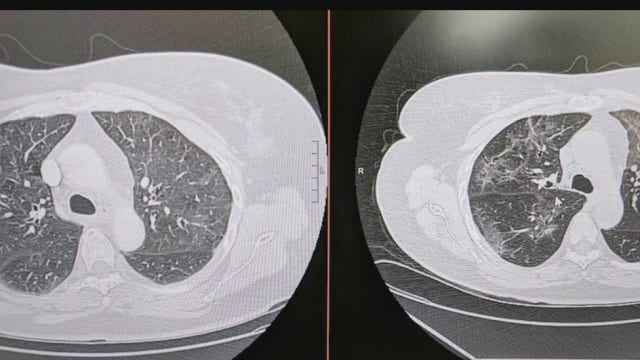

COVID-19 long haulers share experiences of inhalers, hazy lung scans

There are several people who report long-term conditions after battling COVID-19, including hazy lung scans and inhaler usage.